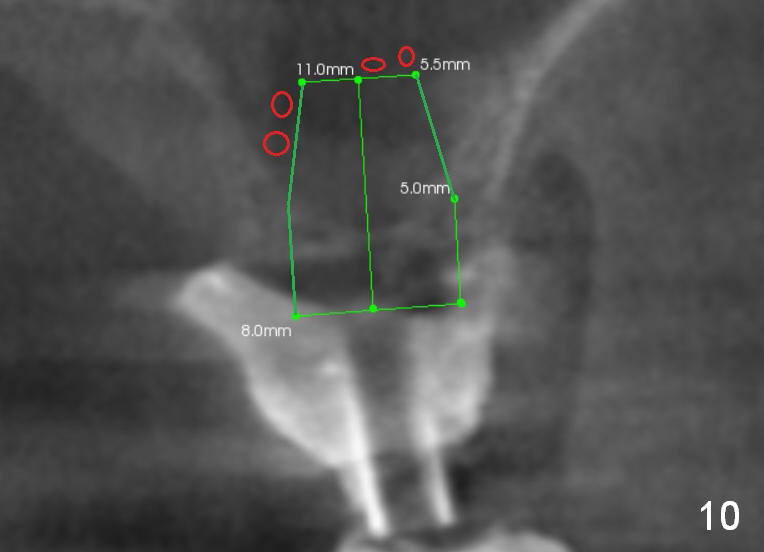

A man in his 70s had a partial denture in the upper left quadrant (Fig.1) prior to loss of #15, which was replaced by an implant (Fig.2). Lateral window sinus graft was tried without success in preparation for $14 implant placeement. Recently the partial was lost. Two missing teeth are going to be restored by implants with sinus lift in the crestal approach. Although the bone height is limited (2 mm), the implant at the site of #14 is able to obtain primary stability by engaging into the sides of the sinus floor (Fig.2 arrowheads).

After crestal incision, a 3.5 or 4 mm trephine bur is used for 2 mm at #14. The regional sinus floor is lifted using a Bicon flat-end osteotome, followed by bone graft and taps. If the 6x11 mm tapered tap does not gain stability (Fig.3), use either 6x11 mm round tap (Fig.4) or 7 or 8x11 mm tapered tap (Fig.5). If the last does not work, try a larger round tap (Fig.6). In all, the sinus floor is pushed upstairs and an implant is inserted to be engaged into the sides of the sinus floor (Fig.7).

Coronally, a round implant does not appear to obtain more bone contact than a tapered one of the same diameter (Fig.8,10). Internal sinus lift works for this case?